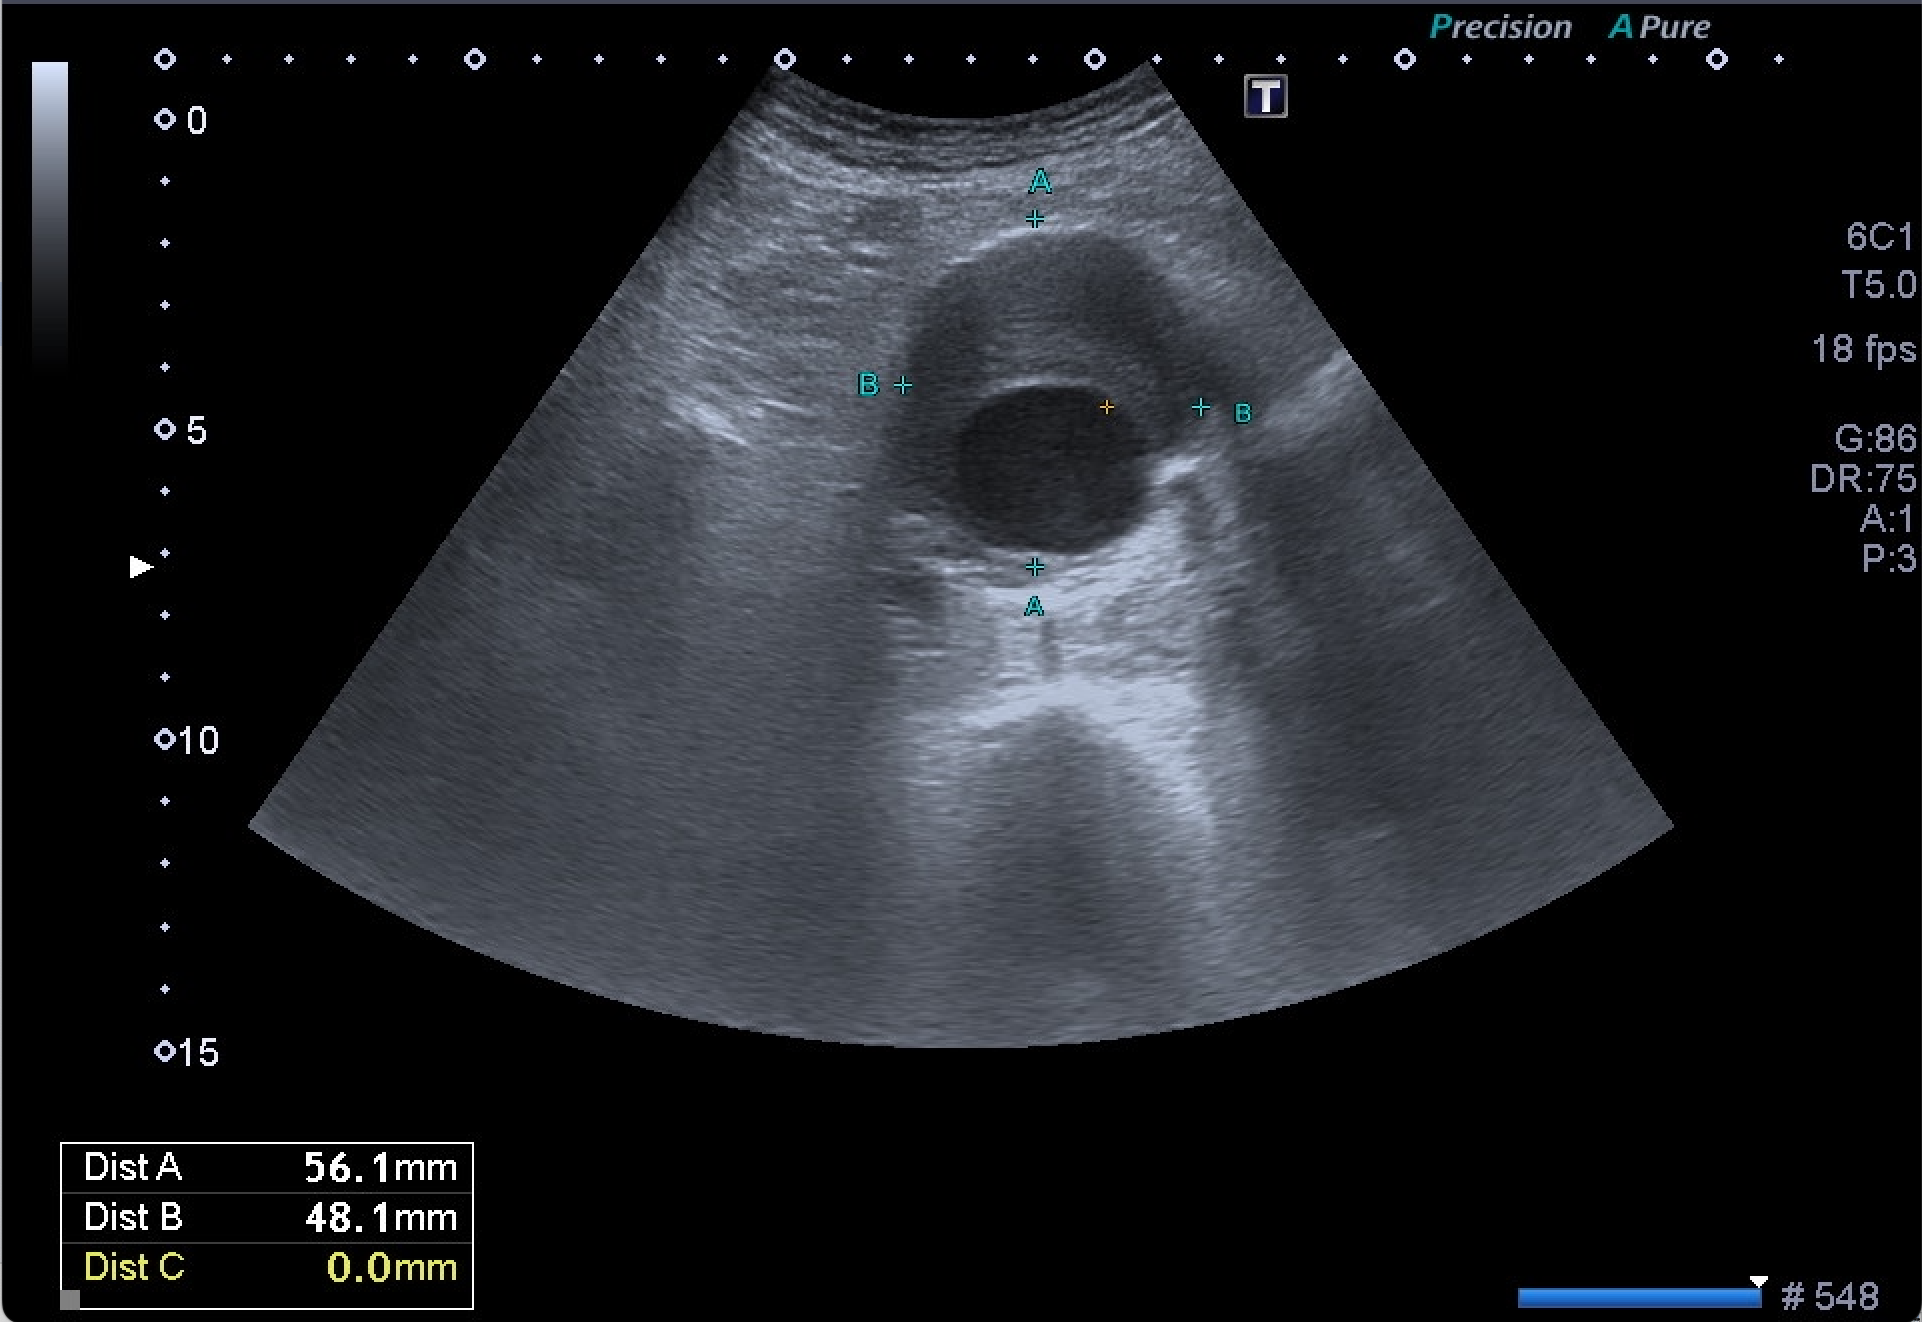

Destaca la visualización de probable litiasis renal derecha, junto con el hallazgo incidental de aneurisma de aorta abdominal, de unos 5,8 cm de diámetro máximo en el plano axial, el cual presenta trombo mural.

Dados los hallazgos, se completa estudio con AngioTC, confirmando la existencia de aneurisma infrarrenal de 6 mm de diámetro mayor, junto con litiasis renal derecha de 5,5 mm y dilatación de la pelvis renal.